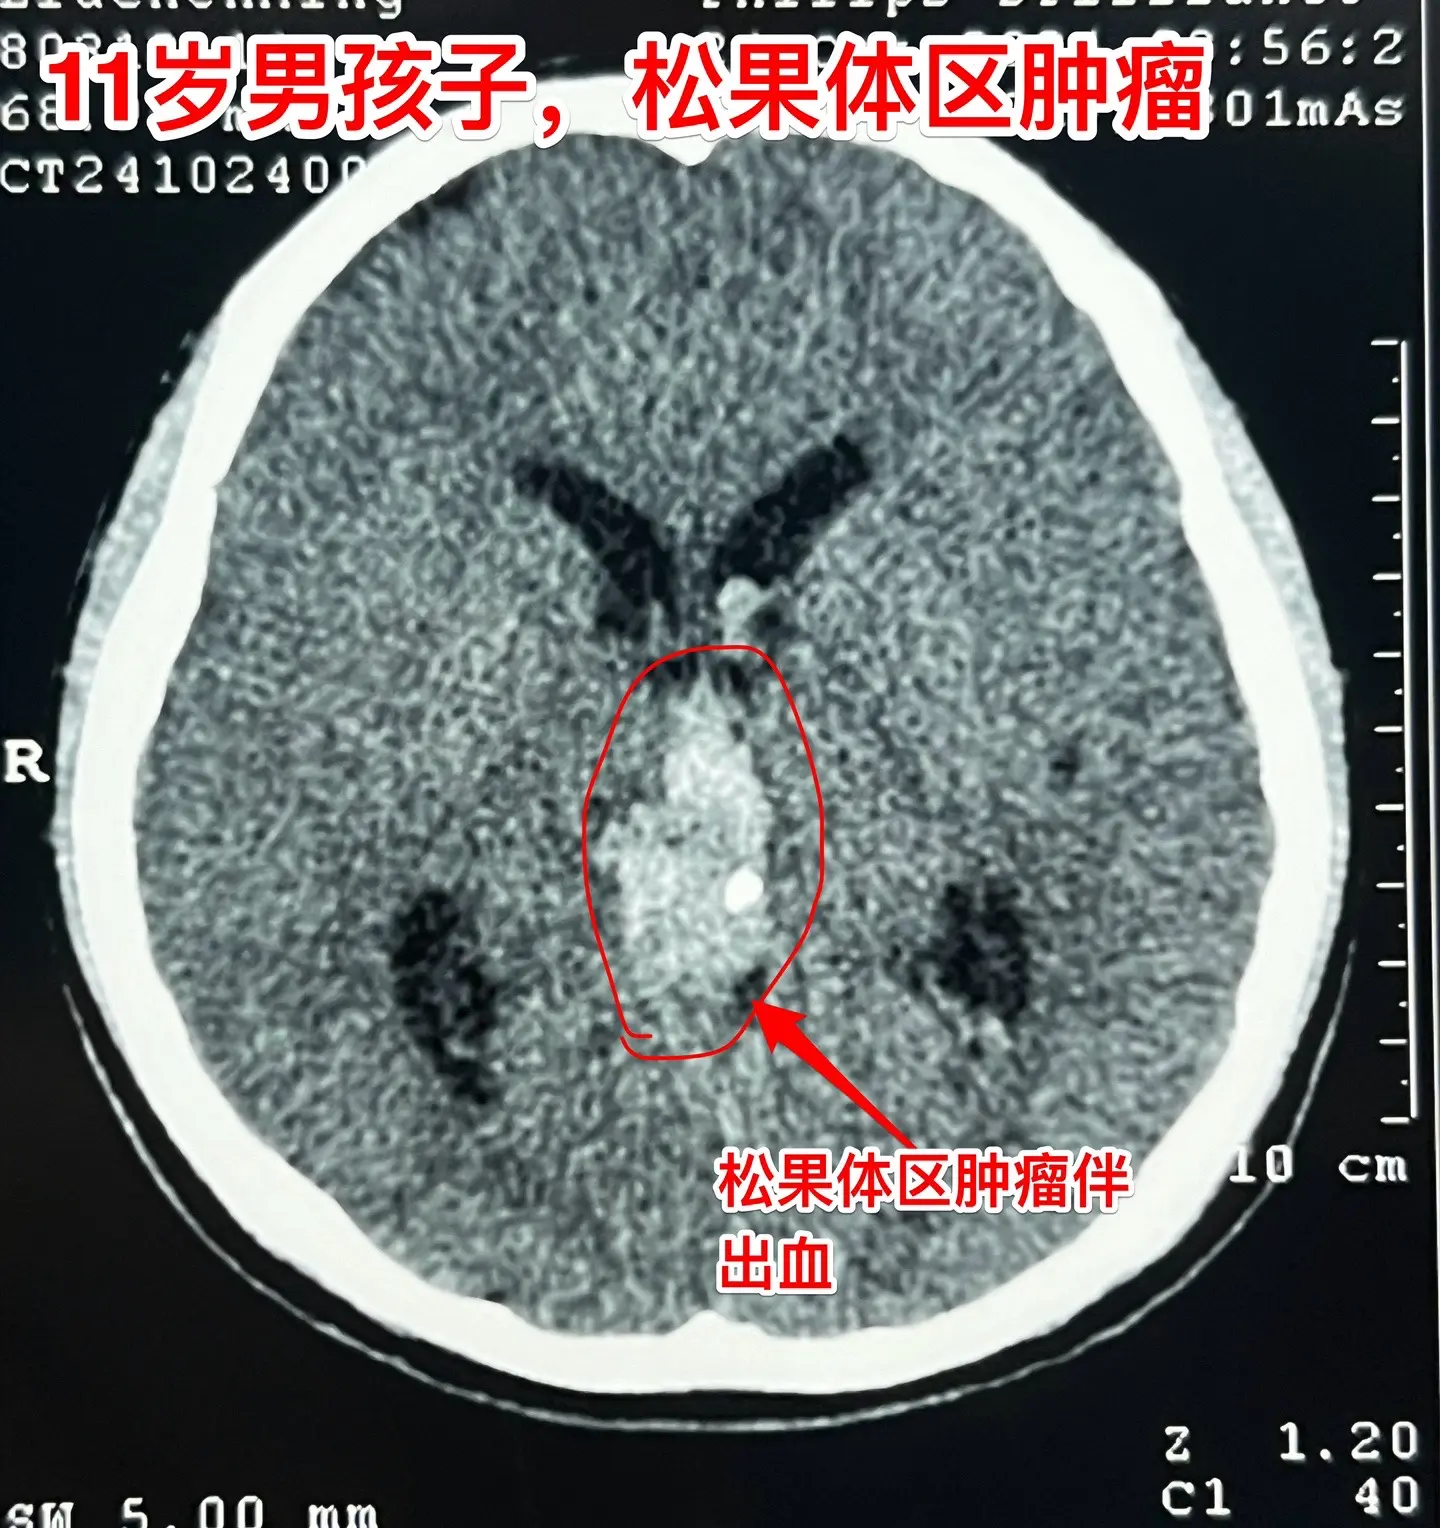

松果体区的绒毛膜癌(绒癌)很罕见。通常情况下,绝大多数的绒癌与女性怀孕过程的滋养细胞有关系,可以造成子宫内出血。 但是,脑部有一种恶性肿瘤称为绒癌,是生殖细胞肿瘤中的一种,很罕见,一般见于鞍区和松果体区。 这个11岁济宁市的男孩子于2024年10月底18日突发头痛、恶心、呕吐,在当地医院行头部CT检查发现了脑部有出血,出血的位置位于松果体区及第三脑室里,和普通的脑出血位置不一样。经过急诊手术(脑室外引流术)后保住了生命。磁共振检查显示松果体区有个肿瘤,考虑是肿瘤卒中出血了。转到我院化验HCG,达到正常值的600多倍。 2024年10月27日在我科作了手术,将肿瘤切除了,手术后小男孩身体恢复顺利,HCG逐步下降到正常范围。病理报告是纯绒癌! 这个脑部的绒癌是生殖细胞肿瘤中的一种,恶性度高,手术后需要作化疗+放疗。